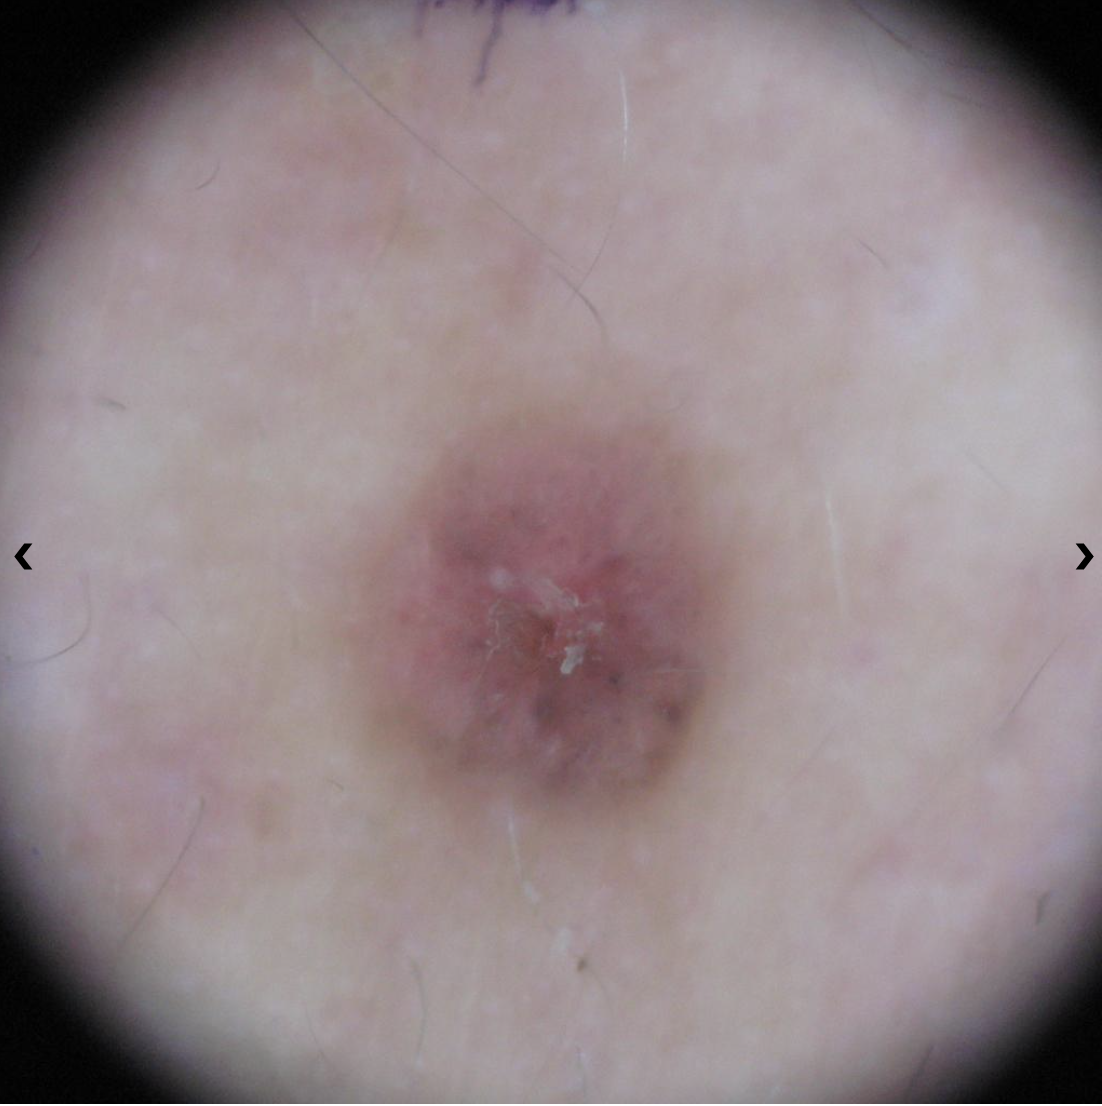

Amelanotic melanomas may be pinkish-looking, reddish, purple, normal skin color or essentially clear and colorless.

Melanoma Photos

Nodular melanoma on the leg of a Native American woman.

Photo: International Skin Imaging Collaboration